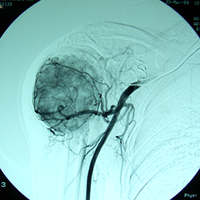

Case:6 Transfer of Scapula to Humerus

Orthopedic Oncology Doctor In Ahmedabad

Angio-2

Limb Reconstruction Doctor

Angiogram